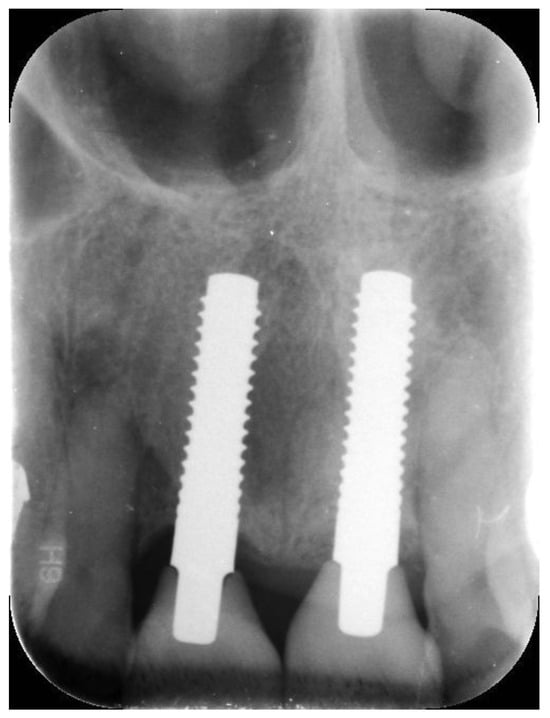

| N | Follow-Up (Months) | Age | Gender | Implant Position | Implant Diameter (mm) | Implant Length (mm) | GBR | Placement Timing (IP/DP) | Loading Timing (IL/CL) | Mean MBL (mm) (T0–T1) |

|---|---|---|---|---|---|---|---|---|---|---|

| 1 | 96 | 42 | F | 11 | 4.1 | 12 | N | IP | IL | 1.9–3.48 |

| 2 | 96 | 59 | F | 21 | 4.1 | 14 | Y | IP | IL | 1.41–1.70 |

| 3 | 94 | 41 | M | 13 | 4.1 | 12 | N | IP | IL | 2.11–3.2 |

| 4 | 92 | 50 | M | 12 | 3.3 | 12 | N | DP | IL | 2.35–3.3 |

| 5 | 83 | 35 | M | 14 | 3.3 | 12 | N | DP | IL | 1.57–1.92 |

| 6 | 88 | 37 | F | 15 | 4.1 | 12 | N | IP | IL | 2.73–2.74 |

| 7 | 73 | 43 | F | 46 | 3.3 | 12 | N | DP | CL | 1.8–1.87 |

| 8 | 73 | 46 | F | 46 | 4.1 | 12 | N | DP | CL | 1.35–1.69 |

| 9 | 62 | 37 | F | 46 | 4.1 | 10 | N | DP | CL | 1.94–2.06 |

| 10 | 59 | 47 | M | 12 | 4.1 | 12 | Y | IP | CL | 0.36–2.03 |

| 11 | 48 | 48 | M | 44 | 4.1 | 12 | N | IP | CL | 2.75–2.86 |

| 12 | 48 | 48 | M | 45 | 4.1 | 12 | N | IP | CL | 2.34–3.24 |

| 13 | 48 | 48 | M | 46 | 4.1 | 12 | N | IP | CL | 3.5–4.19 |

| 14 | 42 | 31 | M | 46 | 4.1 | 10 | N | DP | CL | 1.23–2.03 |

| 15 | 42 | 34 | M | 34 | 3.3 | 12 | N | IP | CL | 1.68–2.32 |

| 16 | 41 | 65 | F | 24 | 3.3 | 12 | Y | IP | IL | 2.1–2.82 |

| 17 | 40 | 64 | F | 21 | 3.3 | 14 | Y | IP | IL | 2.19–3.45 |

| 18 | 38 | 65 | F | 11 | 4.1 | 14 | N | IP | IL | 1.48–2.17 |

| 19 | 33 | 54 | F | 26 | 3.3 | 10 | N | IP | CL | 1.32–1.66 |

| 20 | 30 | 63 | F | 31 | 3.3 | 14 | N | IP | IL | 1.72–1.86 |

| 21 | 27 | 52 | M | 22 | 3.3 | 14 | Y | IP | CL | 1.49–2.53 |

| 22 | 27 | 69 | F | 36 | 4.1 | 12 | Y | DP | CL | 1.72–3.57 |